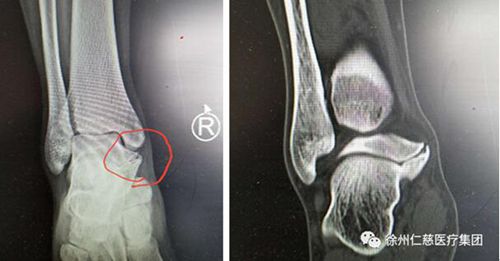

在求治多家醫(yī)院后,本周一上午小朱來(lái)到仁慈醫(yī)院足踝外科專家門診,當(dāng)時(shí)正是業(yè)務(wù)院長(zhǎng)石榮劍坐診,經(jīng)過(guò)詢問(wèn)病史、體檢和X光、CT三維重建,石院長(zhǎng)發(fā)現(xiàn)患者腳里跟骨和距骨間長(zhǎng)出來(lái)了一個(gè)像橋一樣的高密度影,最終診斷是少見(jiàn)的跟距骨橋。

跟距骨橋分先天性和繼發(fā)性兩種,繼發(fā)性跟距骨橋患者一般都有明確的足扭傷病史,患者的主要臨床表現(xiàn)為跟距關(guān)節(jié)內(nèi)側(cè)突起,伴局部壓痛明顯,跑跳時(shí)疼痛加重,中、后足活動(dòng)受限。